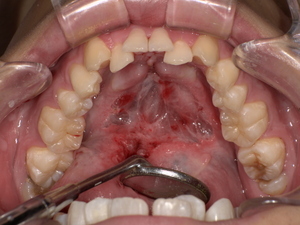

【治療前後の写真】

Before: 舌小帯が短く、舌の可動域が制限されている状態です。このため、舌先を上あごに十分に持ち上げることができません。

[

After: 舌小帯形成術後、舌の動きがスムーズになり、上あごにしっかりと届くようになりました。これにより、発音に必要な舌の動きが改善されます。

]

※写真掲載の際は、患者様の同意を得ています。